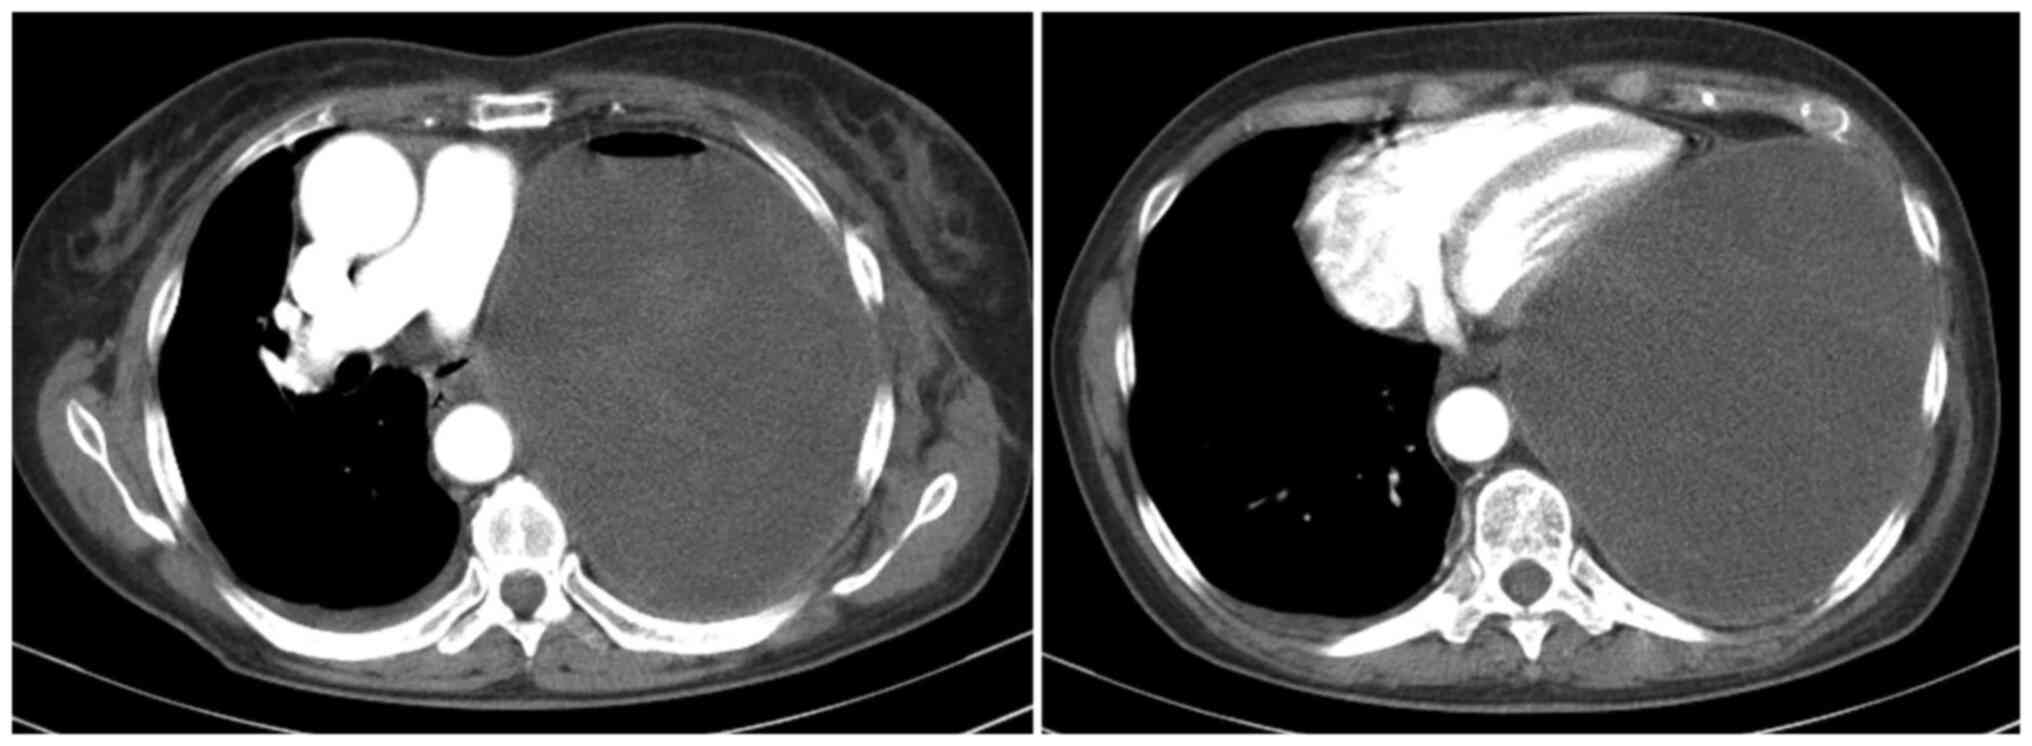

One case of tension haemothorax was reported and the complication appeared almost 1 year after pneumonectomy, causing fatigue, dyspnoea, and oedema of the left arm; internal jugular, subclavian and axillary left veins presented thrombosis; the case was presented by our group in 2014(20) (case 19-Table II). Thoracoscopic evacuation and pleural biopsies were performed. The liquid analysis indicated no malignancy but given the pleural aspect found during surgery, it was deemed to be the mechanism of appearance. However, pleural biopsies proved no malignancy. At four months after therapeutic anticoagulation for the deep venous thrombosis, left haemothorax recurrence developed, with cardiac compression and hypodiastolia (Fig. 3), and emergency evacuation was performed. At present, 8 years after left pneumonectomy, the patient is alive and in a good clinical condition.

Figure 3

CT scan presenting the tension haemothorax case (20)-recurrence 4 months after thoracoscopic evacuation and biopsies, at 1 year and a half after left pneumonectomy for lung adenocarcinoma in a female patient 66y (case 19 from Table II); CT section at the level of the great vessels (left image) and at the level of the heart ventricles (right image).